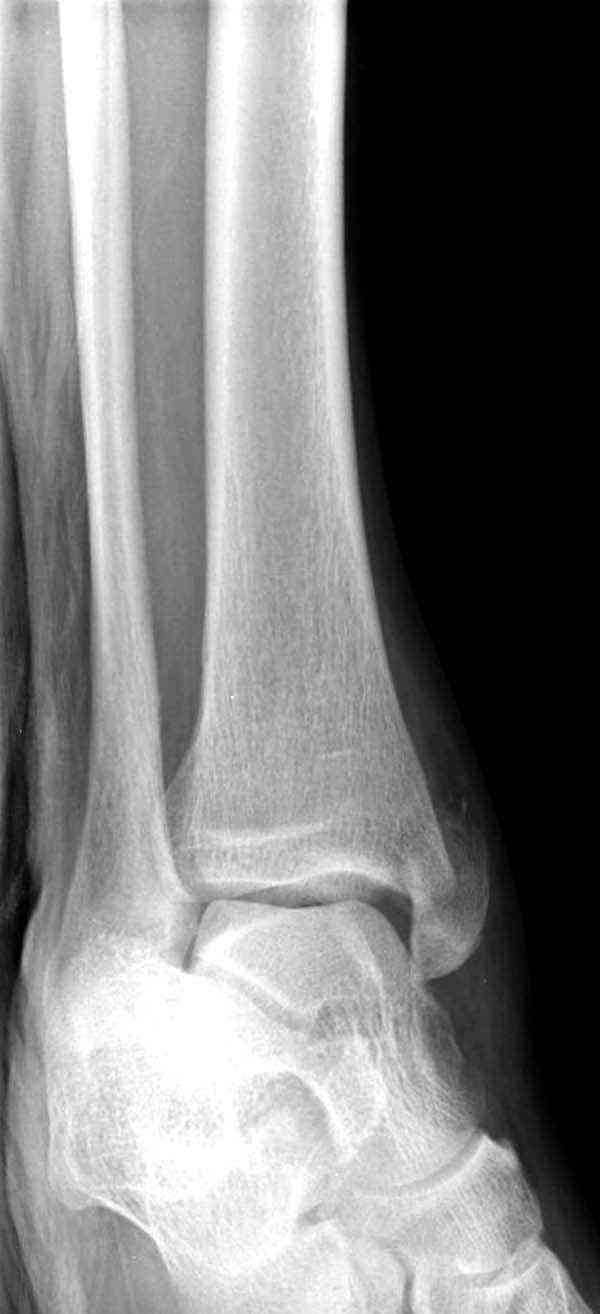

Нет первичных снимков, перелом очень низкий и под большим сомнением диагноз разрыва синдесмоза. Медиальная сторона отрепонирована на "хорошо" и, по-видимому, прорезание проволоки произошло во время операции. Без снимков трудно судить о высоте малоберцовой, а лодыжка находится в варусе. Лагирование получилось, но возле тонких шурупов передне-задний шуруп выглядит немного тяжеловато.

Здесь несколько частных случаев: перелом голеностопа со сравнительными снимками и разрыв синдесмоза, а также медиальная Hook пластина.